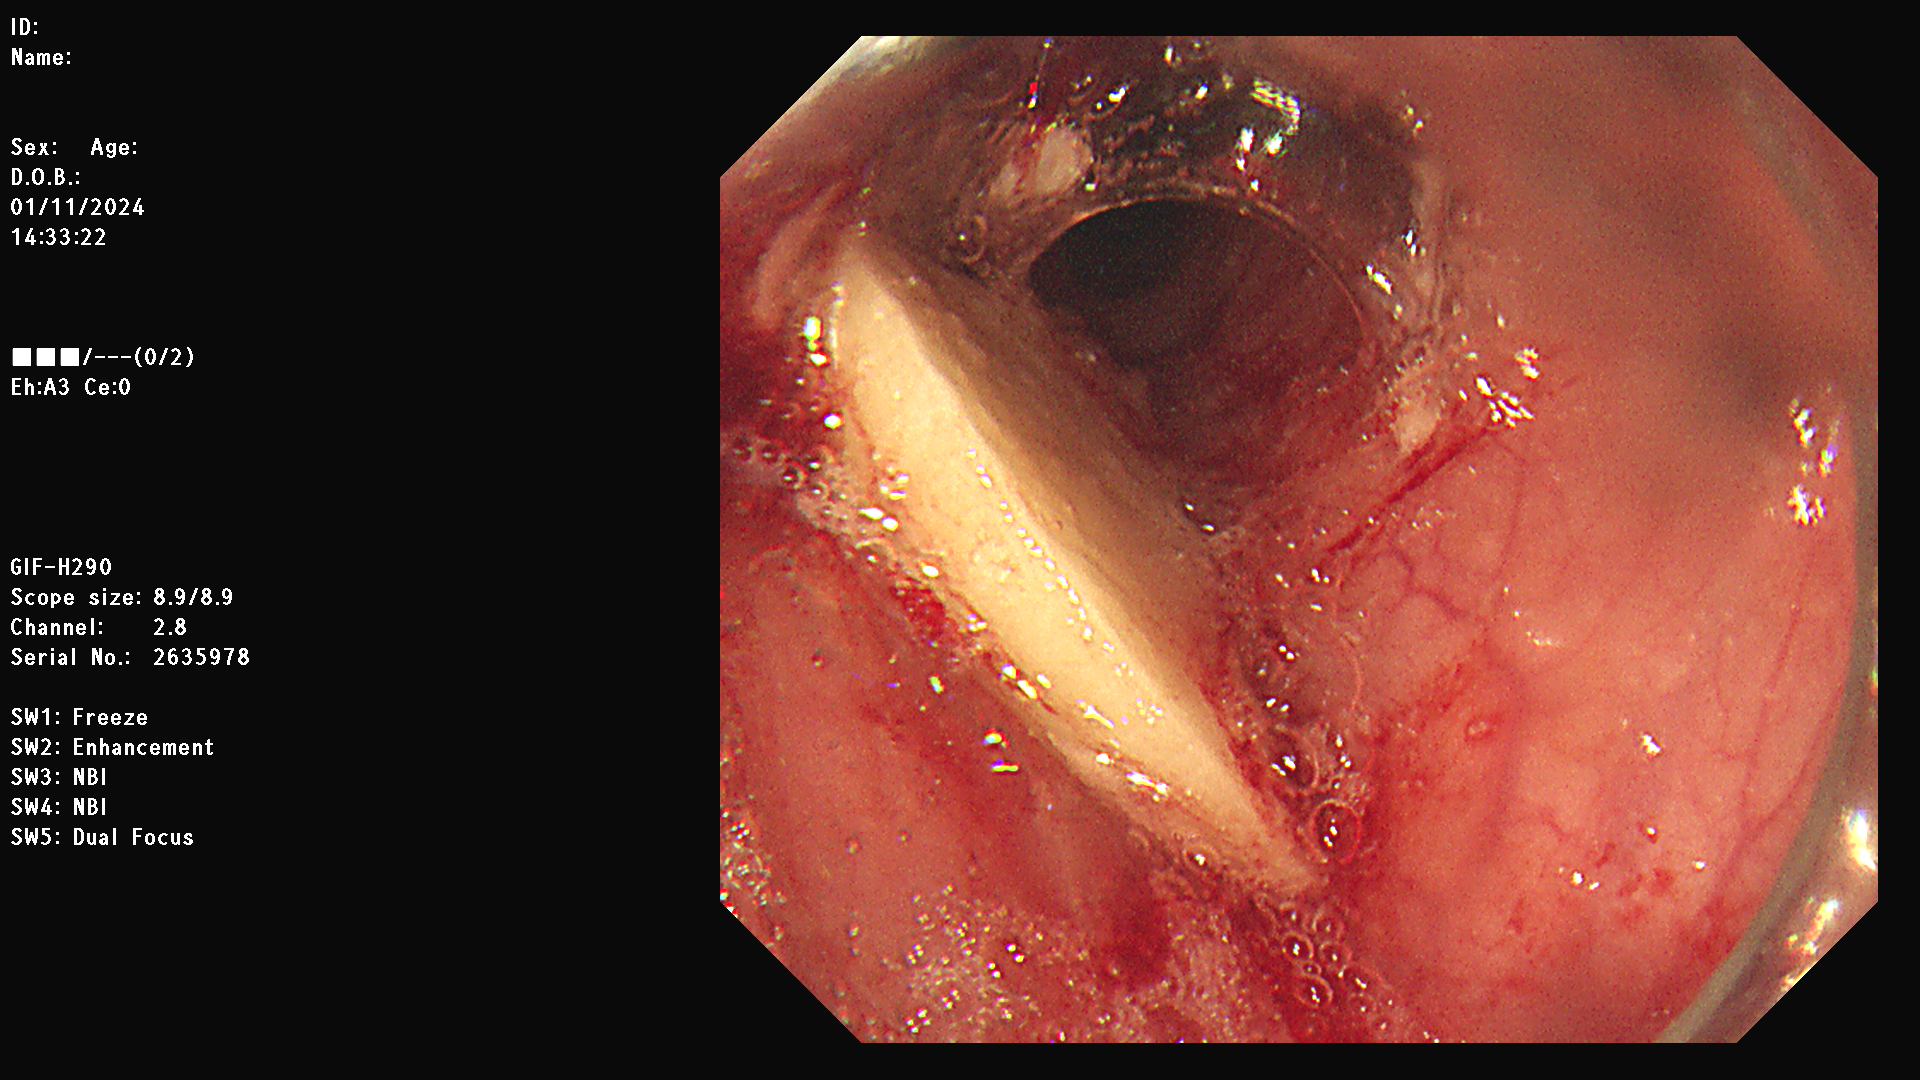

내시경 영상을 확인해보니 뾰족한 뼈로 인해 식도 점막에 상처가 생겨있는 상태였다.

다행히 성공적으로 이물을 제거해냈고

대략 4 x 3 cm 정도 크기가 되는 갈비탕에 들어간 소갈비의 뼛조각이었다.

후일담이지만, 이 환자의 내시경을 한 소화기내과 선생님 말에 따르면 뼈가 식도에 박혀서 꺼내기가 너무 어려웠다고 한다. 대략 1시간 반 동안의 사투 끝에 이물을 제거했다고 하였다.